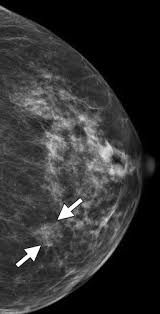

What Does Breast Cancer Look Like On A 3D Mammogram / Mammogram Images Normal And Abnormal - Treatment typically involves some type of surgery and depends upon the staging of the.. The tumor cells don't stay within the clear borders of the mass, but instead invade the nearby breast tissue. The look of breast cancer on a mammogram a tumor or lump will appear as a focused white area on the mammogram. Tumors may be benign or cancerous. Rather than an image that is formed from pictures taken from top to bottom and side to side like a. 3d mammography, or breast tomosynthesis, is a relatively new breast imaging procedure approved by the u.s.

Abnormalities such as cancerous tumors usually appear brighter because they are denser. That makes it easy to detect abnormalities, which generally show up as white. It's so important to listen to the messages our bodies are telling. Ultimately, the news is good: A lump or tumor will show up as a focused white area on a mammogram.

A lump or tumor will show up as a focused white area on a mammogram. It appears to be developing in a concentric pattern. Ultimately, the news is good: These deposits show up as tiny white spots on a mammogram, and there may be only one or two, or too many to count, says jay baker, md, a breast imaging specialist at the duke cancer center.most people assume that what doctors are looking for on a mammogram are lumps, dr. However, when the breast is compressed from top to bottom, the tissue in the upper breast can overlap tissue in the lower breast. What does breast cancer look like on a mammogram? Any area that does not look like normal tissue is a possible cause for concern. Screening mammograms have been used since the 1980s.

Benign, noncancerous masses can appear as a focal asymmetry. Breast cancer can present either as an area of focal asymmetry or when advanced can even present as a new asymmetry in breast size. Images are displayed as a series of thin slices that can. The outer edges of these cells look fuzzy or spiky (called spiculated). What does breast cancer look like on a mammogram? Diagnostic mammograms involve taking more views than screening mammograms. What does breast cancer look like on a mammogram? Not all women have calcifications in their breasts—but most do. This is why you should always talk to your doctor if you notice an unexplained change in the size of a breast. Ultimately, the news is good: Rather than an image that is formed from pictures taken from top to bottom and side to side like a. Even if you have a lump in only one breast, pictures will be taken of both breasts. They will look carefully at the mammogram to interpret the results.

The outer edges of these cells look fuzzy or spiky (called spiculated). A false positive is when a mammogram shows an abnormal area that looks like a cancer but turns out to be normal. Most screening mammograms include two views of each breast taken from different angles. A lump or tumor will show up as a focused white area on a mammogram. They will look carefully at the mammogram to interpret the results.